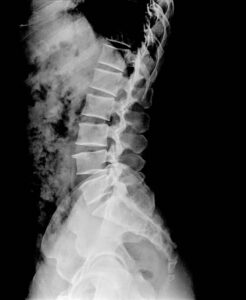

A myelogram is a specialized diagnostic imaging procedure that uses contrast dye injected into the spinal fluid, followed by CT imaging, to evaluate the spinal cord, nerve roots, and spinal canal. This advanced imaging technique provides detailed information that helps diagnose the cause of back pain, neck pain, and neurologic symptoms.

Myelograms diagnose spinal conditions by revealing abnormalities in the spinal canal, spinal cord, and nerve roots that may not be fully visible on standard imaging.

Myelograms are highly accurate for visualizing the spinal canal, nerve roots, and areas of compression.